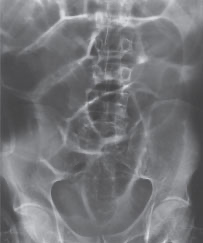

<p>How would the pathology evident be categorized?</p>

How would the pathology evident be categorized?

Destructive